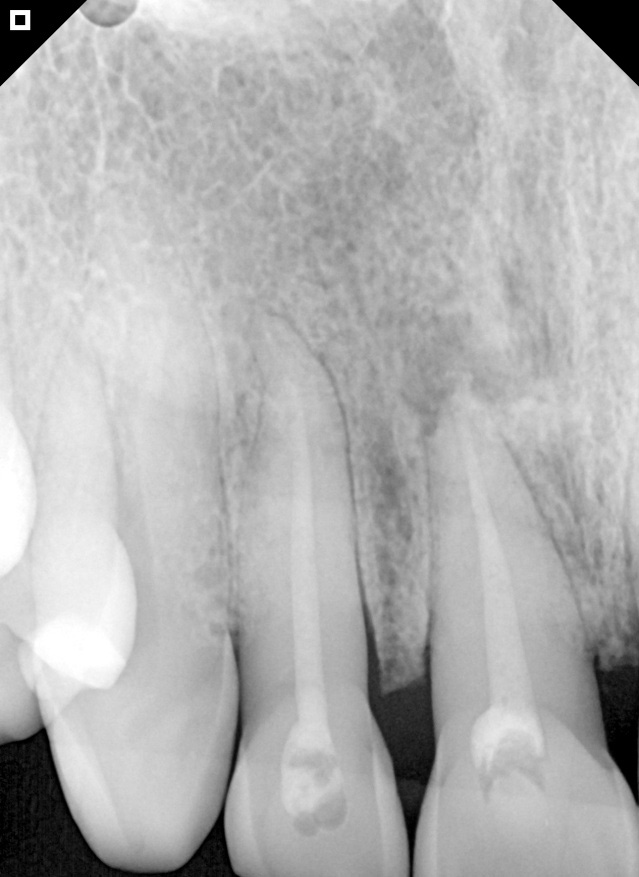

Initial radiography.